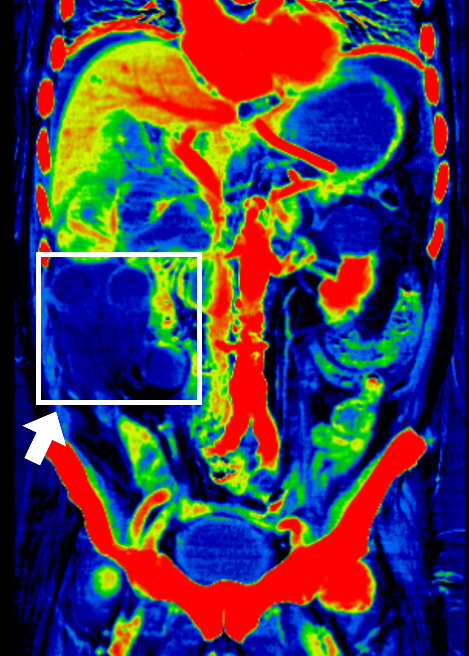

腸管虚血の症例を以下に提示します。

Frontier_Hachiojiiryo_04.png

腹部造影撮影の平衡相(造影剤注入後120秒)をデュアルエナジーで撮影した画像です。矢印部分に虚血領域を認めます。ヨードマップにてヨード集積を強調し、さらにカラー表示を併用することによって、視認性の高い画像を提供できるため、救急対応のDrからも高い評価を頂いています。

スペクトラルイメージング技術により、検査から治療までに要する時間が短縮し、迅速な治療が求められる救急領域に対し非常に効果的であると感じています。